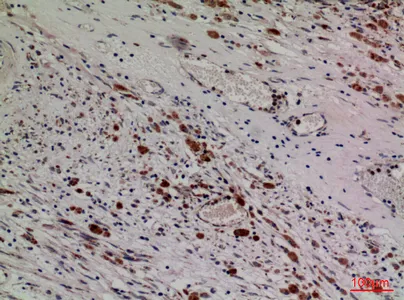

TNF-α Rabbit Polyclonal Antibody

Cat: APRab19095

Size1:50μl Price1:$118

Size2:100μl Price2:$220

Size3:500μl Price3:$980

Size2:100μl Price2:$220

Size3:500μl Price3:$980